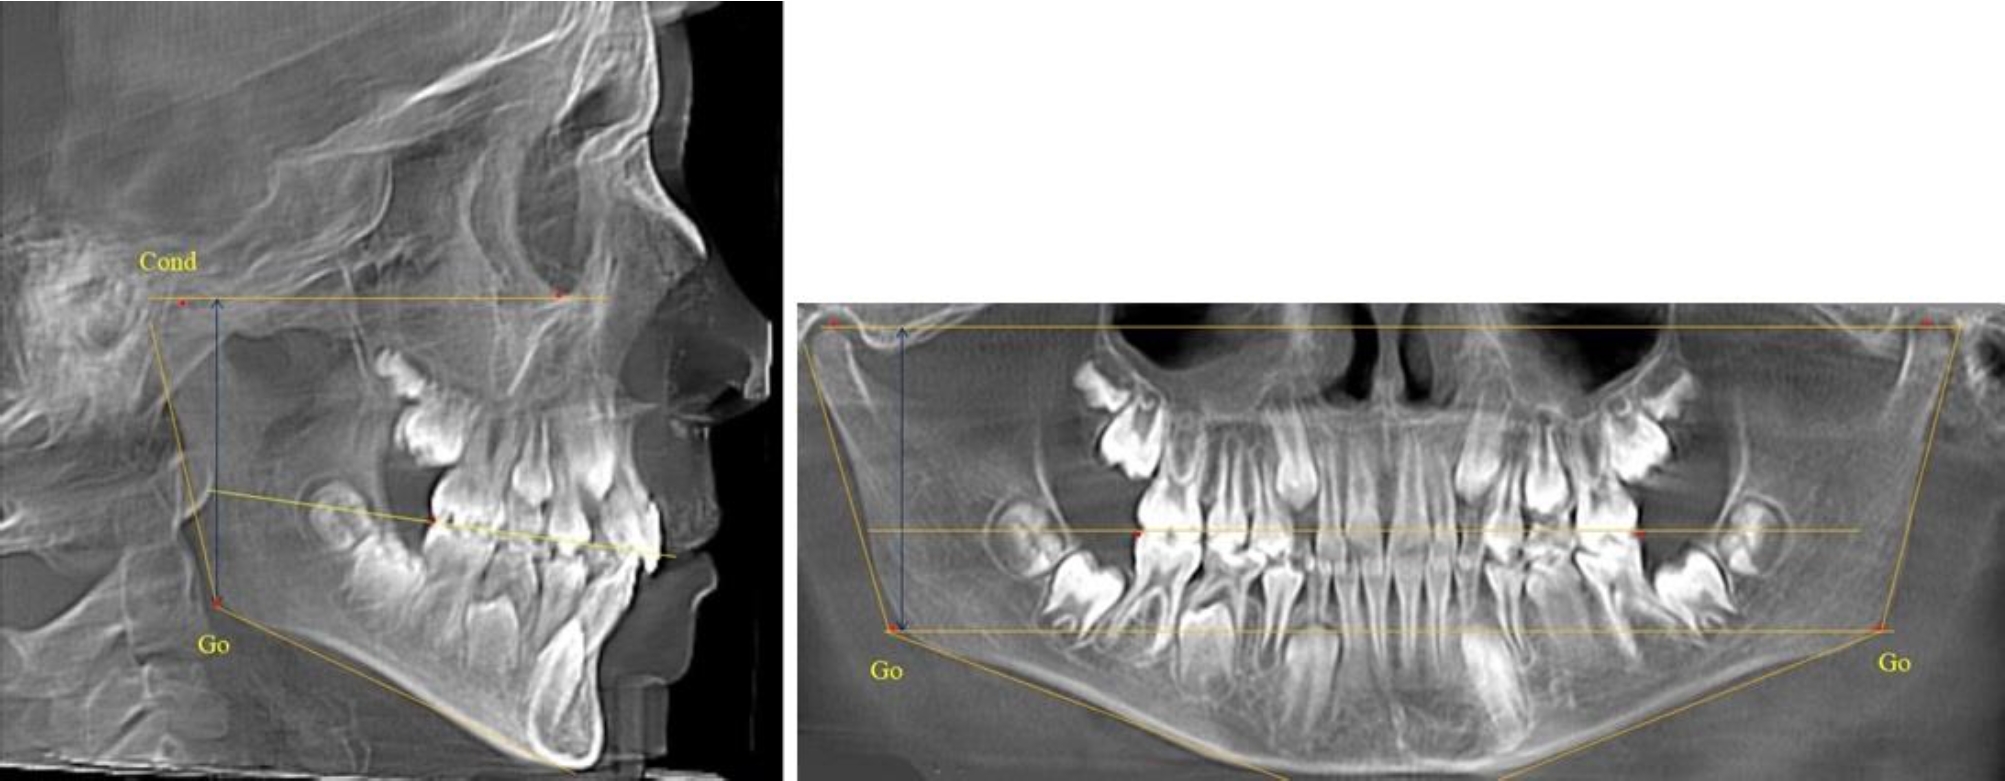

В 1-й группе были проанализированы 7 телерентгенограмм и 7 ортопантомограмм, что составило (6,60 ± 2,41) % от числа изученных рентгенограмм. На всех парах рентгенограмм угол нижней челюсти, измеренный на телерентгенограмме, соответствовал углу, полученному при построении угла на ортопантомограмме. Окклюзионная линия практически однотипно делила ветвь на два отдела (рис. 1).

Как на ортопантомограмме, так и на телерентгенограмме высота ветви у детей в периоде сформированного прикуса молочных зубов составляла (42,21 ± 2,48) мм. При этом высота верхней окклюзионно-суставной части была (22,57 ± 1,46) мм, а нижней – (19,64 ± 1,54) мм.

Учитывая вариабельность абсолютных величин, определи относительные показатели соразмерности частей ветви нижней челюсти. Так, отношение высоты верхней части ветви к нижней в среднем составляло 1,15 ± 0,13. Отношение общей высоты ветви к верхней ее части составляло 1,87 ± 0,14, а отношение общей высоты ветви к нижней ее части было 2,14 ± 0,16 и достоверных различий по относительному показателю отношения всей высоты к верхней и нижней челюсти нами не отмечено (р ˃ 0,05). При этом визуально обе части выглядели примерно равноразмерными.

Рис. 1. ТРГ и ОПТГ пациента 1-й группы